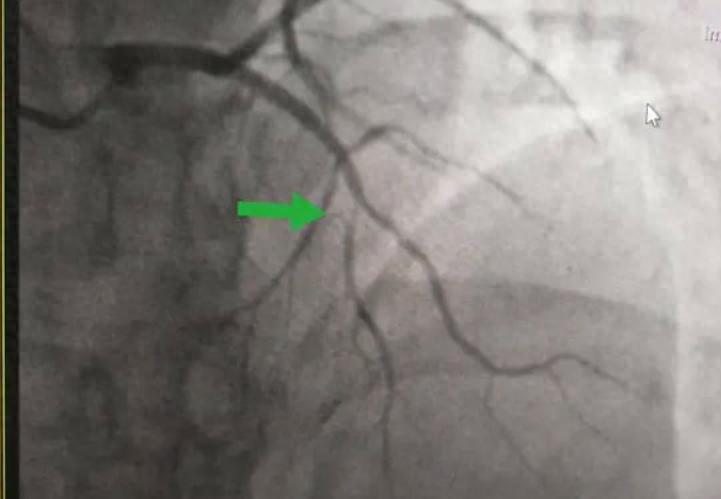

冠脉造影是一项诊断冠脉疾病非常有效的技术,它利用血管造影仪器,然后通过特定型号的导管,将其经皮穿刺进入下肢的股动脉,沿着患者的主动脉进入升主动脉,然后找到左右冠脉插口,注射造影剂,这样的话冠脉造影就能很好的成像了。

冠脉造影的出现,主要就是为了看清楚冠状动脉的病变,因此帮助诊断应该是冠脉造影技术出现的主要原因。那么它的适应症有哪些?